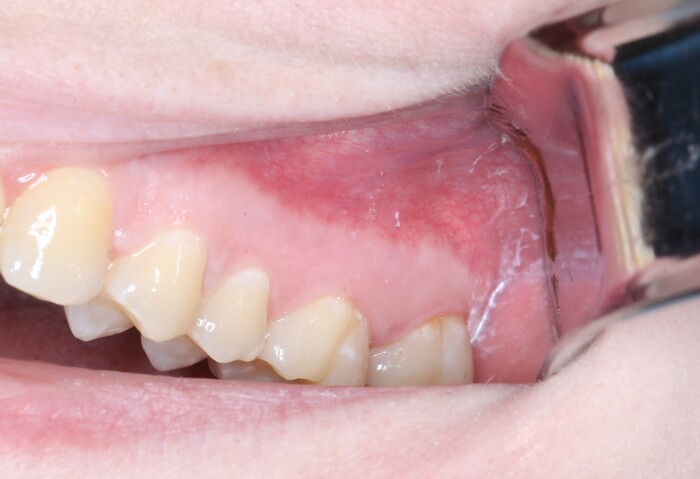

Вот так выглядит область, в которую мы планируем вмешаться:

А для таких:

Чуть меньше часа (отдельно верх, отдельно низ):